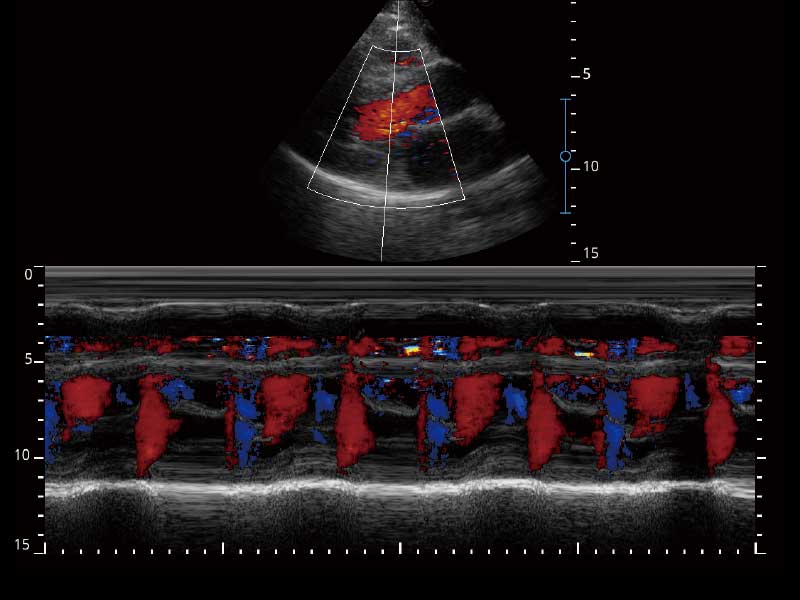

PW自动包络分析,对血流动力学指数快速测量,自动生成结果,同时也支持可编辑的手动包络功能,对感兴趣区域进行单独分析,提高诊断准确率。